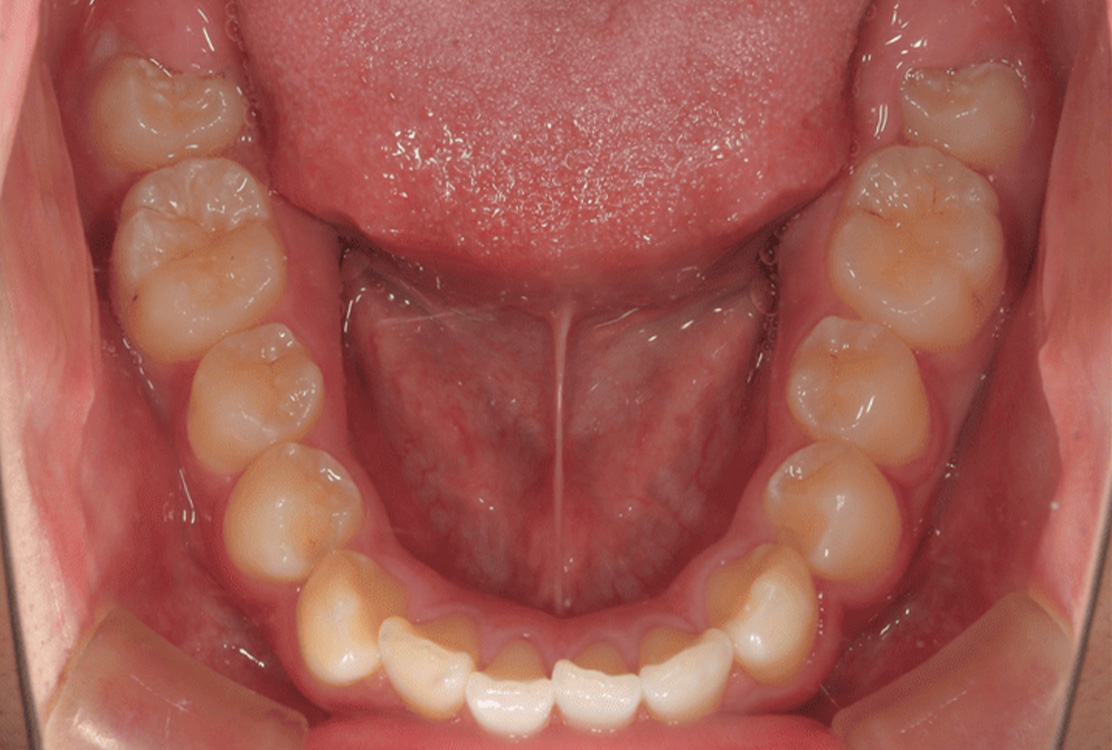

治療後